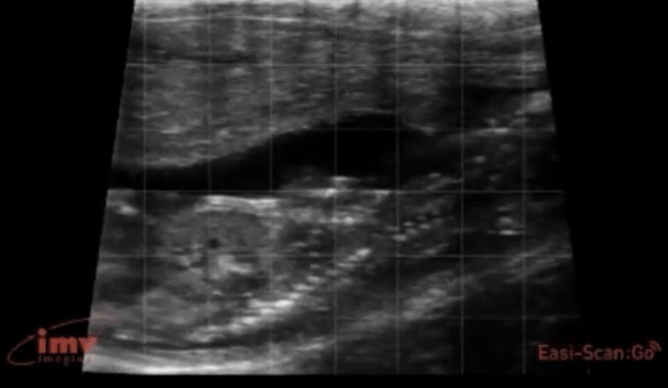

Our view of a calf foetus at various gestation stages: